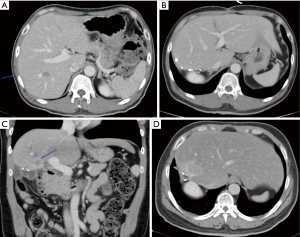

While ALPPS may be able to provide the surgeons with a better chance of securing an R0 resection for HCC, the selection of patients remains the key consideration. In the first international expert meeting on ALPPS, HCC was listed as one of the pathologies where ALPPS procedure should be used with caution due to higher morbidity and mortality rate (113). Laparoscopic ALPPS can potentially confer additional benefit as it harnesses the benefits of minimally invasive surgery (MIS) with smaller scars, lesser post-operative pain, faster recovery and shorter hospitalisation (Figure 4A,B,C,D,E,F).

The feasibility of MIS liver resection depends very much on the location of the lesions and their relationship with major structures such as the portal vein, hepatic artery, bile ducts and hepatic veins. In many cases, the lesions could be present in multiple locations and laparoscopic HPB surgeons need to have a strategy tailored to individual patients to achieve R0 for all the lesions, at the same time, leaving behind sufficient FLR for survival of the patients in the immediate post-operative period. Even when the lesions are located at very difficult locations (e.g., at caudate lobe in segment I of liver, Figure 5A,B,C), advances in surgical instruments have made it possible to perform the surgery laparoscopically with very high success rate.